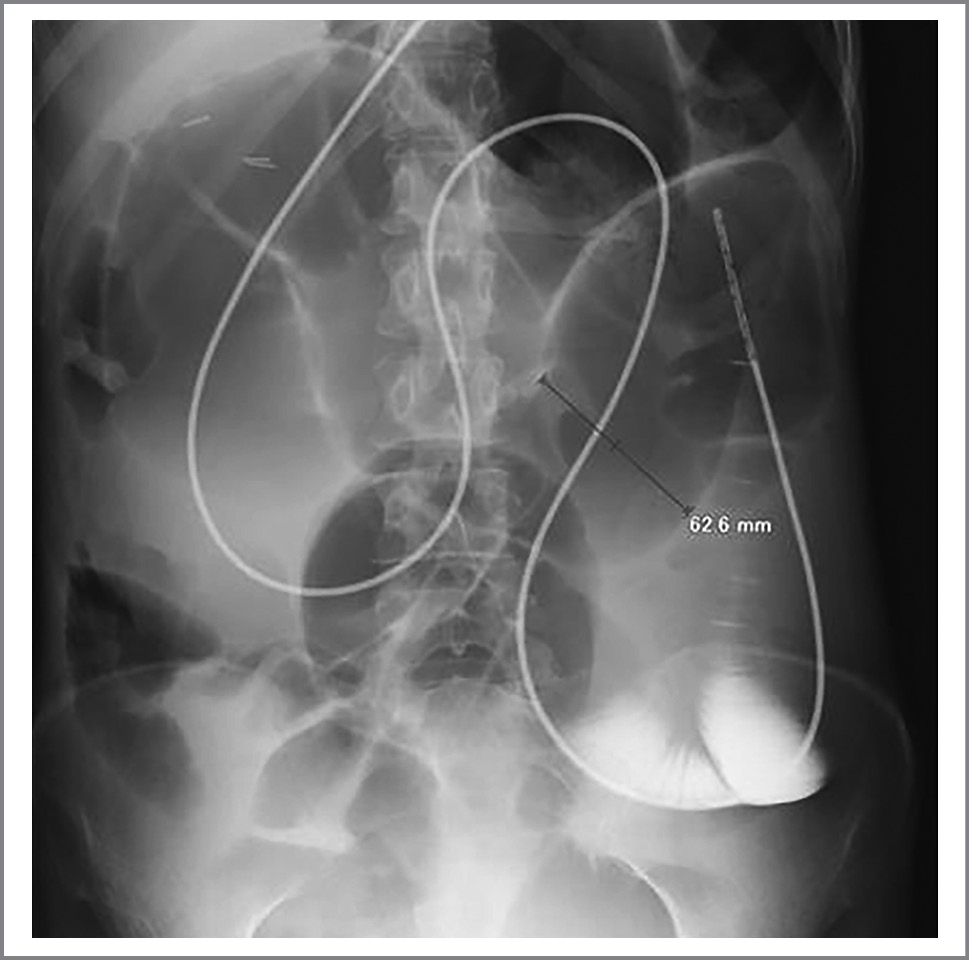

Для обеспечения адекватного энтерального питания больной установлен назоинтестинальный зонд. На рис. 4 показано положение зонда. Через зонд контрастированы петли тощей кишки, диаметр которой неравномерно расширен от 30 до 63 мм, в них определяются скопление газа и жидкости (горизонтальные уровни). Петли толстой кишки не расширены, спавшиеся. Заключение: рентгенологическая картина тонкокишечной непроходимости.

Рис. 4. Рентгенограмма больной А.: брюшная полость с назоинтестинальным зондом.

Fig. 4. X-ray of patient A.: abdominal cavity with nasointestinal probe.